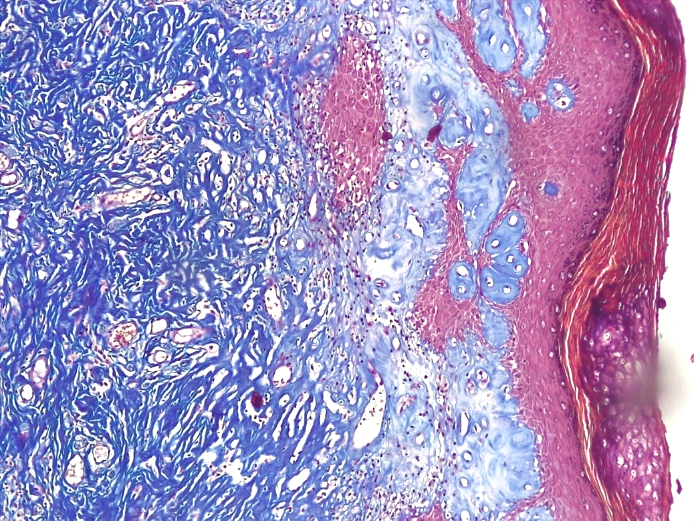

Что касается состояния микроциркуляторного русла при склерозирующем варианте течения СЛВ, то количество кровеносных сосудов было резко редуцировано как в поверхностных, так и в глубоких отделах дермы. В стенках кровеносных сосудов отмечалось развитие склероза и гиалиноза, что указывало на длительное нарушение сосудистой проницаемости в этой зоне (рис. 10 и 11).

Рис.11. Склерозирующий вариант СЛ вульвы. Резкая атрофия клеток эпидермиса с участками гиперкератоза с выраженным фиброзом поверхностных и глубоких слоев дермы со склерозом и гиалинозом немногочисленных сосудов микроциркуляторного русла (окраско по пикро-Маллори, х200)

Fig.11. The sclerosing variant of the vulva SL. Sharp atrophy of epidermal cells with areas of hyperkeratosis with pronounced fibrosis of the superficial and deep layers of the dermis with sclerosis and hyalinosis of a few vessels of the microcirculatory bed (picro-Mallory coloring, x 200)